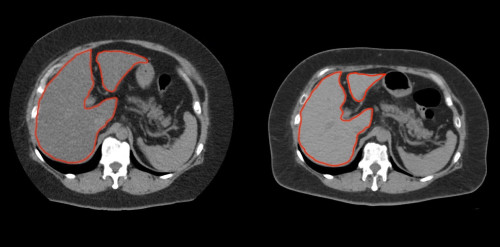

①

50代・女性(ご本人のご厚意で画像提供)

治療内容:チルゼパチド7.5mgの週1回自己注射による脂肪減少と脂肪肝改善

治療期間: 12ヶ月(52週)((用量は2.5mgから開始し最大で15mg。減量効果が得られる必要用量には個人差があります。))

1:脂肪の減少

皮下脂肪の減少(赤色部分)

2:脂肪肝の改善

沈着した脂肪の減少による肝臓の平均CT値の増加(20から50へ)(脾臓の平均CT値は両者とも50)

bluntness of the liver edgeの改善(青色部分)